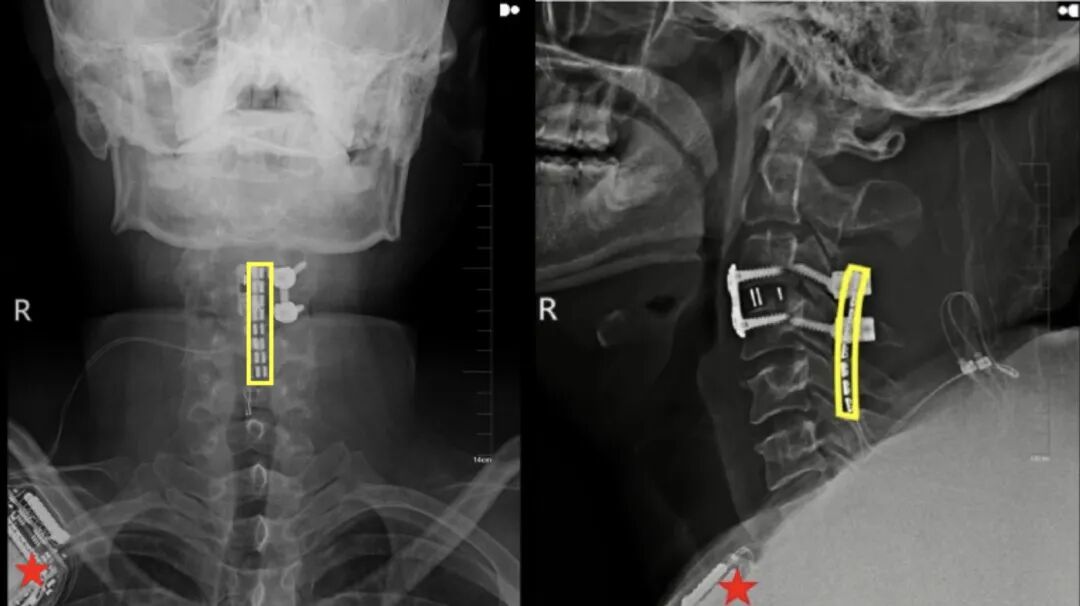

先生是在执行公务时不幸被车撞伤,被紧急送往吉大二院后检查发现,他的肺损伤严重,存在大量胸腔积液,同时三严重骨折错位,呼吸衰竭,生命垂危。

骨折错位指的是第三颈椎C3发生了骨折且出现椎体位置异常,因涉及高位颈脊髓,是极其危重的医疗情况。“很多颈四以上损伤的患者,甚至都来不及送到医院,当场就去世了。”吴敏飞告诉“医学界”。

挽救生命是当务之急。刘先生入院后,吉大二院立即启动重伤救治绿色通道,由吴敏飞主刀完成神经减压内固定术。

值得一提的是,手术中,吴敏飞考虑到后续存在着脊髓神经接口植入的可能,同步在颈椎损伤段预留了一个“接口”。

手术非常成功,术后一个月,刘先生的恢复情况良好,生命体征保持稳定。但由于颈椎严重损伤致完全性截瘫,他的脖子以下彻底失去了运动能力和感觉,大小便失禁。